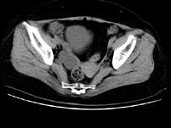

- 单项选择题女,27岁, 体检时B超发现右侧附件区囊性占位性病变,CT检查如图, 下列说法错误的是 ( )

A、病灶来源于右侧卵巢

B、病灶边界清晰

C、病灶为单房,壁薄,无分隔

D、考虑为卵巢浆液性囊腺瘤

E、考虑为卵巢囊肿